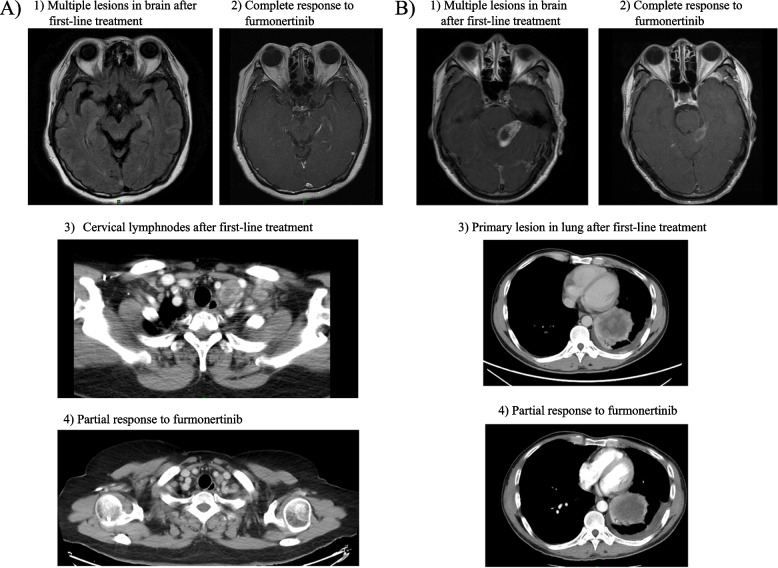

In the BM cohort, patients with an ECOG-PS of 0–1 achieved a significantly longer iPFS than those with a poor physical status (PS 2–3), which was 14.6 months (95%CI 0.000–32.594) and 2.1 months (95%CI 1.152–3.128), respectively (P = 0.023). In the LM cohort, the majority of patients (87.5%) had a poor physical status prior to furmonertinib treatment, therefore no significant difference was observed between patients with different status (P = 0.791). In addition, the survival analysis in patients who had received third-generation TKI rechallenge (including patients with or without other treatments in between) seemed to have an inferior iPFS compared to those who had not, while no significant difference was observed in each cohort. As for treatment strategies after CNS progression to prior TKI, the combination of furmonertinib 160 mg and bevacizumab/anlotinib has improved the iPFS compared to single agent in the BM cohort, with the median iPFS of 9.6 months (95%CI 0.000–21.322) and 2.3 months (95%CI 1.605–2.895), respectively, although no significant significance was observed (P = 0.104). However, no similar trend was observed in the LM cohort (P = 0.903). The subgroup analysis above was shown in Fig. 2. Two typical cases in the BM cohort and the LM cohort who were successfully treated with furmonertinib 160 mg and bevacizumab were presented in Fig. 3, and the treatment strategies for patients who had adchived an iPFS of more than 6 months were presented in Supplementary Table 1.

Fig. 3.

Typical examples in (epidermal growth factor receptor) EGFR-mutant non-small cell lung cancer (NSCLC) patients successfully treated with furmonertinib 160 mg as salvage treatment who had intracranial progression to prior tyrosine kinase inhibior (TKI). A A female patient had extracranial progression along with newly-diagnosed brain metastases (BM) and leptomeningeal metastases (LM) after first-line chemotherapy and afatinib. A secondary genetic test has shown EGFR exon 19del mutation (73.8%), EGFR exon20 T790M mutation (28.7%), and EGFR amplification (CN = 11.9). The patients then received furmonertinib 160 mg combining with bevacizumab as second-line treatment, and had a significant improvement in dizziness which was related to her central nervous system (CNS) disease. The targeted lesion in her brain had a complete response (CR), and the metastatic cervical lymph nodes also had a partial response (PR). 1) Multiple lesions in brain after first-line treatment; 2) Complete response to furmonertinib; 3) Cervical lymphnodes after first-line treatment; 4) Partial response to furmonertinib. B A male patient diagnosed as advanced EGFR-mutant NSCLC with BM received afatinib as first-line treatment for 14 months, and had an intracranial progression and edema with severe CNS-related symptoms such as fatigue and vomiting. A gene detection at progression showed EGFR exon19 deletion mutation (1.36%) and TP53 mutation (0.85%), whereas no T790M mutation in circulating tumor DNA (ctDNA). The patient then received furmonertinib 160 mg and bevacizumab along with radiotherapy in CNS. The targeted lesion in her brain and the primary lesion in lungs had a PR, and her symptoms were significantly relieved. 1) Multiple lesions in brain after first-line treatment; 2) Partial response to furmonertinib; 3) Primary lesion in lung after first-line treatment; 4) Partial response to furmonertinib